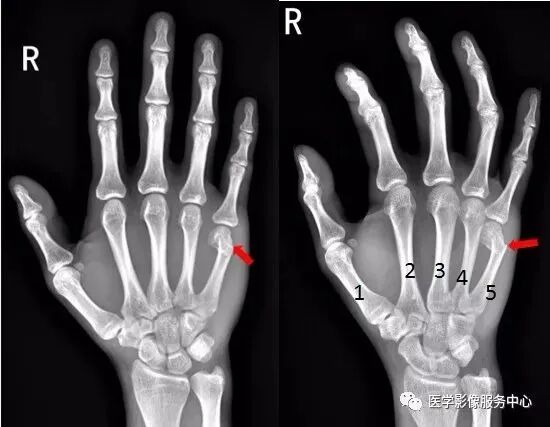

(一)手部

右手拇指远节指骨甲粗隆游离骨碎片影

右手第五掌骨远端骨皮质不连续,骨折端移位、成角。右手第五掌骨骨折(1-5. 第1-5掌骨)